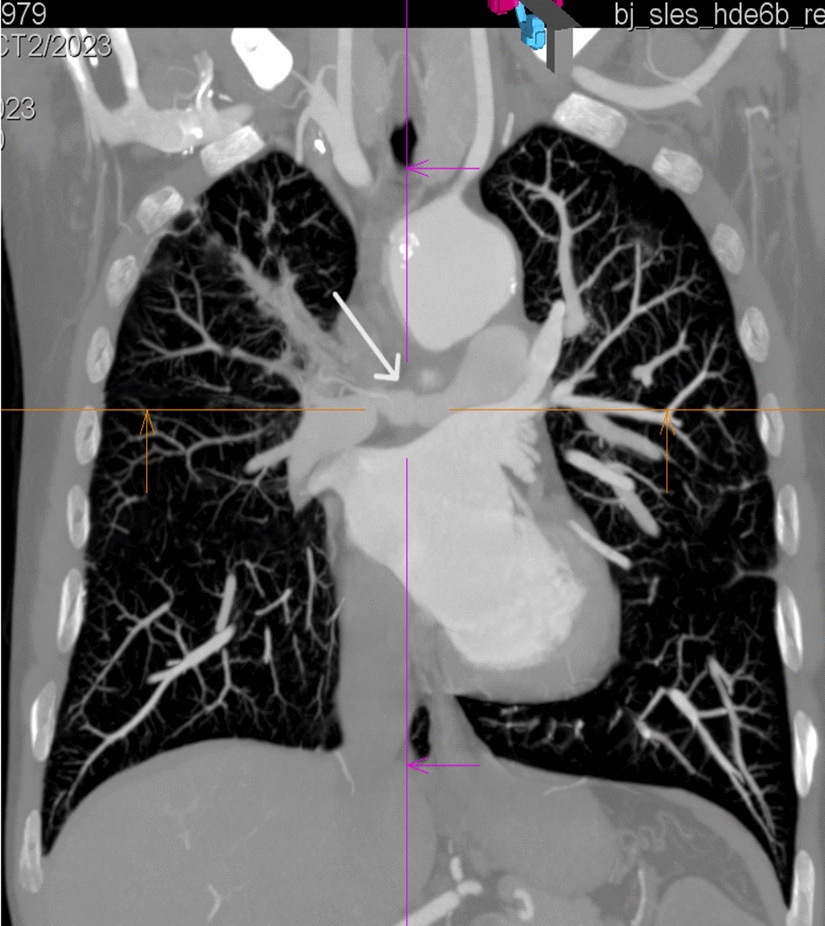

Currently in 2019 the patient reported weakness, worsening exercise tolerance, shortness of breath, dry cough, and joint pain that had been present for approximately two months. A few days before admission to the Rheumatology Clinic, night sweats and fevers up to 39 degrees occurred. Patient's general condition was average; in the physical examination abnormalities included the presence of a systolic murmur over the heart, a diminished vesicular murmur with single crackles over the left lower lung field, generalized muscle atrophy, and effusion in the left antecubital bursa with the presence of purulent content. Laboratory tests showed elevated inflammatory parameters [C-reactive protein (CRP) 94 mg/l (normal: 0–5 mg/l), erythrocyte sedimentation rate (ESR) 66 mm/h (normal: 1–10 mm/h)], anaemia [hemoglobin level 11.6 g/dl (normal: 14–18 g/dl)]. In serological tests the level of PR3-ANCA antibodies was increased compared to the last measurement—46 RU/ml (normal: 0–19.99 RU/ml). Staphylococcus aureus was cultured in the material from the elbow bursa and ceftriaxone was used for treatment, resulting in reduction of inflammation parameters and resolution of the exudate. Additionally infection with the influenza A H1 N1 was confirmed in the sputum material and oseltamivir was added to the treatment. A chest CT scan was also performed, which revealed new changes of the ground glass type in the lower lobe of the right lung and fresh multiple"star"densities were found in segments 4 and 5 of both lungs. There was a progression in the lung image compared to the previous examination performed two years earlier. A cardiac ultrasound examination revealed typical changes for right ventricular overload, and pulmonary hypertension was suspected. CT angiography showed a narrowing of the right pulmonary artery by approximately 85% of the cross-sectional area to 6 mm (2 years earlier 16 mm) and of the pulmonary trunk and left pulmonary artery by approximately 30–40%. (Fig. 1) In magnetic resonance angiography a muff with thickening of the wall of the pulmonary trunk and the right and left pulmonary arteries in their initial sections were also visualized. The features of the muff were similar to those observed in Takayasu's disease or other large vessel vasculitis (LVV). Right heart catheterization revealed elevated pulmonary artery pressure that did not meet the criteria for pulmonary hypertension. Considering the overall clinical picture, the patient was diagnosed with the exacerbation of GPA in the form of pulmonary arteritis and lung involvement, the viral etiology of pulmonary lesions was also taken into account in the differential diagnosis. Due to the lack of enlarged peripheral lymph nodes and a normal ultrasound image of the liver and spleen, we did not extend the diagnostics towards lymphoma. The patient scored 5 points on the Birmingham Vasculitis Activity Score (BVAS). The BVAS result in our case does not reflect the actual disease activity because it does not take into account inflammation of the pulmonary arteries. The dose of glucocorticosteroids used in the treatment was increased to 0.5 mg/kg body weight, the dose was reduced due to iatrogenic Cusching's syndrome with severe complications in the form of osteoporosis complicated by fractures of the Th12-L4 vertebral bodies and ribs and avascular necrosis of the right femoral head. The patient was enrolled in the next course of rituximab treatment according to the schedule of four infusions at a dose of 375 mg/m2 body surface area, at weekly intervals.

Fig. 1

White arrow shows a narrowing of the right pulmonary artery wall in angio-CT scan from 2019